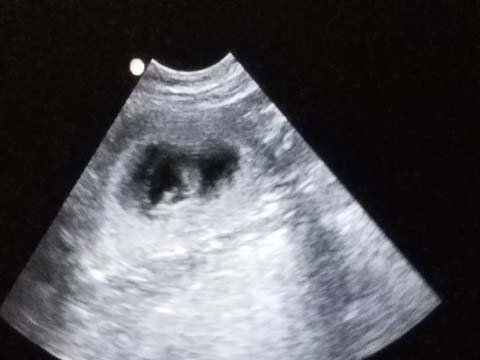

********************************************************************************************* RJ and Turquoise, Winter 2019 Three Pups Born November 14 2019 Two Males, 1 Female All Pups Have Gone to Their New Homes ![]()